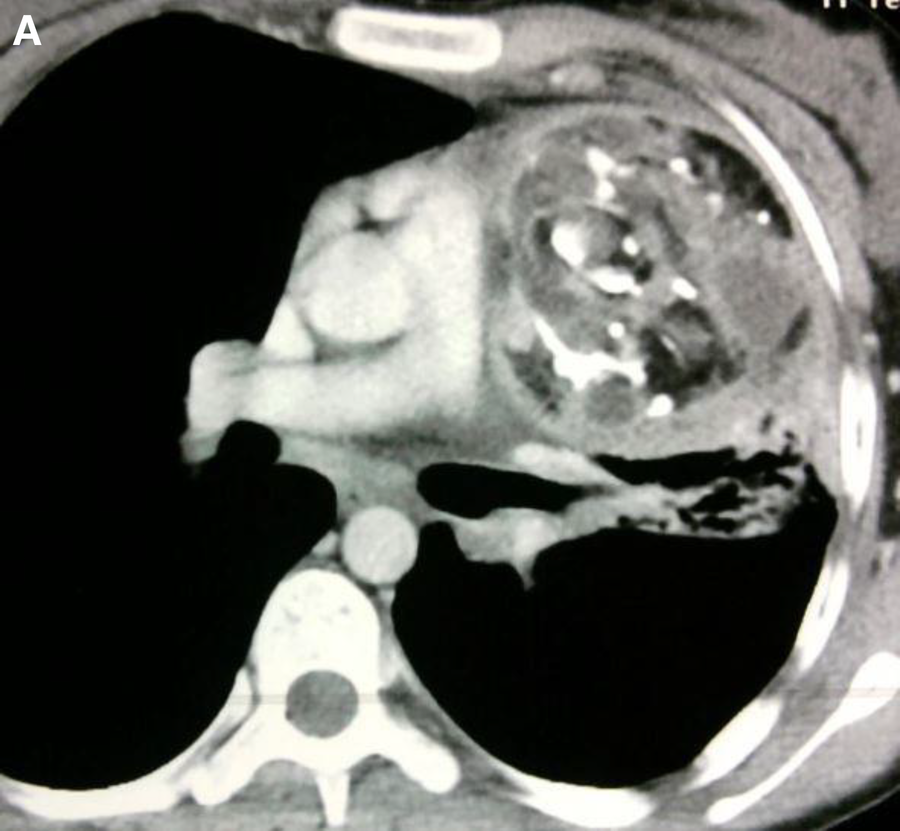

Figure 13

Cardiac Hemagioma in a 40 years old male. In Right ventricle there is round contrast enhancing lesion, involving the right ventricular cavity shown in Figure A is cardiac hemangioma.

Figure 14

A mature teratoma in a 16 years old female patient. (A). Contrast enhancing CT chest showing a calcified, fatty lesion inside heart, calcifications are multifocal representing huge mature cardiac teratoma.